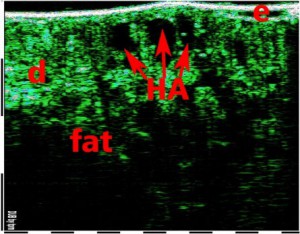

-Έγχυση Πληρωτικών Υλικών (Fillers)